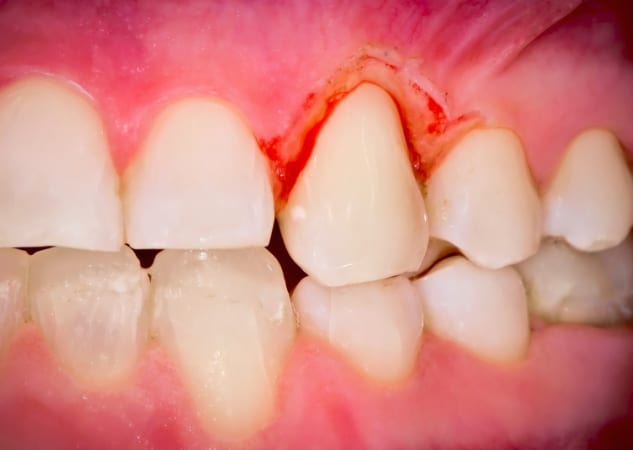

Para que puedas identificarlo visualmente, te ponemos algunas fotos de casos de gingivitis y periodontitis:

Gingivitis